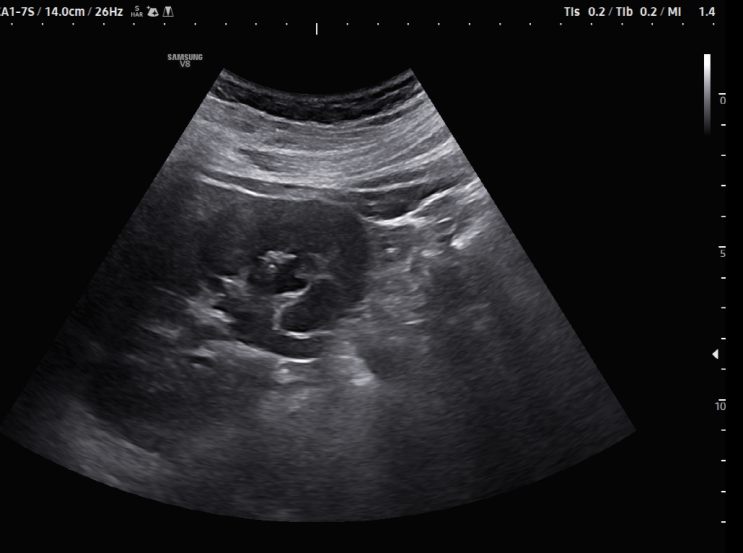

[왕십리 급성복통]서울으뜸내과, 비만 환자에서 진단하기 어려웠던 급성충수염 증례

#급성충수염 #복부초음파 #Convexprove #서울으뜸내과 #왕십리내과 #상왕십리내과 #하왕십리내과 #도선동...